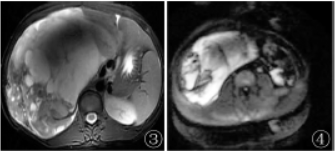

MRI检查:右侧腹膜后可见巨大团块状囊实性异常混杂信号影,呈T1WI等低、T2WI高等低信号(图3)、DWI高低混杂信号(图4),其内可见多发分隔影,增强扫描实性部分及分隔呈渐进性持续明显强化(图5,6),囊性部分未见明显强化。

图3 T2WI显示病变内信号不均匀;图4 DWI病变呈不均匀高信号;图5,6增强冠状位及轴位扫描显示病变呈不均匀强化;

在MRI由于肿瘤成分不同,信号表现为多样化,在T1WI主要呈低或等信号,少数可见稍高出血信号,T2WI主要呈高信号或混杂信号,部分瘤内可见T2WI高信号分隔,DWI呈高信号,增强扫描肿瘤实性部分呈不均匀延迟强化,另外,少数肿瘤周围可见包膜,T2WI序列呈环形低信号。UPS较特征性的表现是坏死囊变及特征性的“假包膜征”、“纤维分隔征”、“尾征”。

本例为青年女性,临床表现为腹胀,影像检查提示腹膜后巨大团块状不均匀软组织密度/信号影,增强扫描呈不均匀强化,可见坏死囊变,与上述影像表现基本一致。